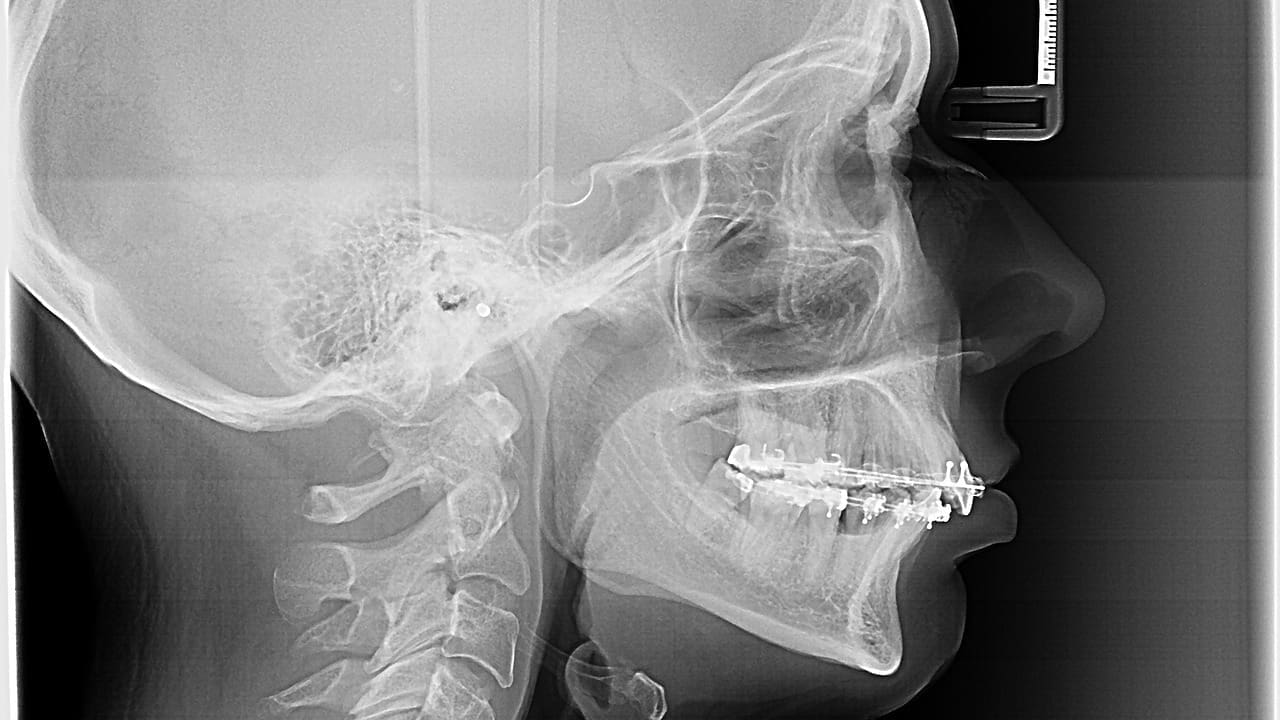

Plates, Screws, and Cages

Surgeons use plates, screws, and cages to stabilize the spine. These tools help keep the spine aligned and aid in fusion.

| Plates and Screws | Metallic devices for spinal stabilization | Maintain spinal alignment during fusion |